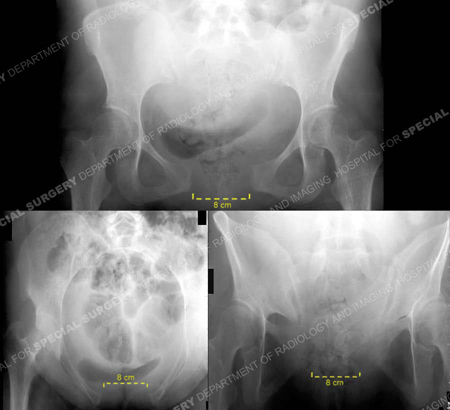

Diagnostic work-up included standard radiographs of the pelvis demonstrating widening of the symphysis pubis of 9 cm and opening of both sacroiliac (SI) joints posteriorly. A CT scan using 2 mm thin cut technique was performed to evaluate the posterior pelvic ring and SI joints. The CT scan demonstrated bilateral sacroiliac joint disruptions. In addition, a MRI scan documented disruption of the pelvic floor and extensive hematoma. Imaging studies revealed an unstable pelvic dislocation with significant symphyseal widening and disruption of the posterior pelvis equivalent to an APC III, or Tile Type C pelvic injury. Open reduction and internal fixation (ORIF) of the pubic symphysis was performed with placement of a contoured 5-hole 3.5 mm pelvic reconstruction plate and screws. Anatomic reduction and stabilization of SI joints were performed using bilateral posterior ilio-sacral screw arthrodesis. Under fluoroscopic control bilateral single 7.3 mm cannulated screws were inserted percutaneously into the body of S1. The perioperative course was unremarkable. She followed up at regular intervals and reported progressive resolution of pain symptoms. The SI screws were removed at 2 years due to mild radiographic evidence of screw loosening. She returned at 2.5 months following hardware removal and reported complete pelvic pain relief and return to pre-injury activities.

Pelvic views 3 days following vaginal delivery. Anteroposterior, inlet, and outlet views (counter-clockwise) demonstrate separation of the symphysis pubis. The symphysis is separated 9.5 cm and the sacroiliac joints are widened. The left SI joint demonstrates displacement of 9 mm, and the right 8 mm in width. No fractures are identified.